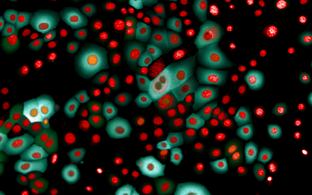

Tartu Ülikooli geeni- ja arvutiteadlaste uurimus lisas kindlust väitele, et ravimi toime sõltub geneetilistest markeritest.

Teadlased vaatlesid koos Eesti geenidoonorite geeniandmeid, nende manustatud ravimeid ja haigusjuhtumeid ning tuvastasid seose ravimite kõrvalmõjudega. Näiteks avastati üks geenivariant, mille kandjate seas esines märksa rohkem lihasvalu pärast põletikuvastase ravimi tarbimist.

Uurimistöös kasutati rohkem kui 16 000 geenidoonori tervise- ja geeniandmeid.